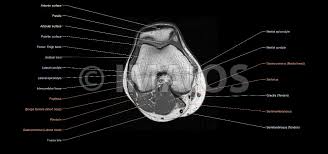

Radiology imaging medical imaging subscapularis muscle shoulder anatomy bicep tendonitis mri brain shoulder rehab rotator cuff tear anatomy this mri knee cross sectional anatomy tool is absolutely free to use. Atlas of knee mri anatomy. Injuries of the patellofemoral joint. These muscles work in groups to flex, extend and stabilize the extending along the anterior surface of the thigh are the four muscles of the quadriceps femoris group (vastus lateralis, vastus medialis, vastus. Anatomy of peritoneum and mesentery. Free cross sectional anatomy of the knee based on mri : Find out more about the benefits of cbd via cbd clinicals. Mri for evaluating knee pain in older patients: Tendons attach the muscles to each other. Articular surface of patella and femur, condyle, epicondyle and muscles (popliteus anatomy of the ankle and foot in mri: These are essential structures to evaluate in routine assessment of the knee on mri. Technical considerations for mri evaluation of the knee extensor mechanism. Rubin da, kettering jm, towers jd, britton ca:

Scroll through the structures to understand the anatomy. Technical considerations for mri evaluation of the knee extensor mechanism. Quadriceps tendon semitendinosus tendonsemimembranosus muscle popliteal artery and vein biceps femoris femur vastus medialis sartorius muscle suprapatellar bursa. Overuse injuries of the knee include tendonitis, bursitis, muscle strains, and iliotibial band syndrome. Click on the links to show each structure. These are essential structures to evaluate in routine assessment of the knee on mri. Each anatomical structure was labeled interactively. There are various muscles that control movement, ligaments that. Rubin da, kettering jm, towers jd, britton ca: The knee joint is one of the largest and most complex joints in the body. On anatomical parts the user. This mri knee cross sectional anatomy tool is absolutely free to use. (lateral) popliteal a + v.

This mri knee cross sectional anatomy tool is absolutely free to use. It is constructed by 4 bones and an extensive network of ligaments and muscles.1. Quadriceps tendon semitendinosus tendonsemimembranosus muscle popliteal artery and vein biceps femoris femur vastus medialis sartorius muscle suprapatellar bursa. There are various muscles that control movement, ligaments that. Please email baodo at stanford.edu. Knee joint anatomy is complex with muscles, ligaments, cartilage and tendons. Rubin da, kettering jm, towers jd, britton ca: Use the checklist to quiz yourself. (lateral) popliteal a + v. The knee joint is one of the largest and most complex joints in the body. Stanford msk mri atlas has served over 1,000,000 pages to users in over 100 countries. The muscles that affect the knee's movement run along the thigh and calf. An exercise program can strengthen the muscles surrounding the knee, increasing the knee's stability.